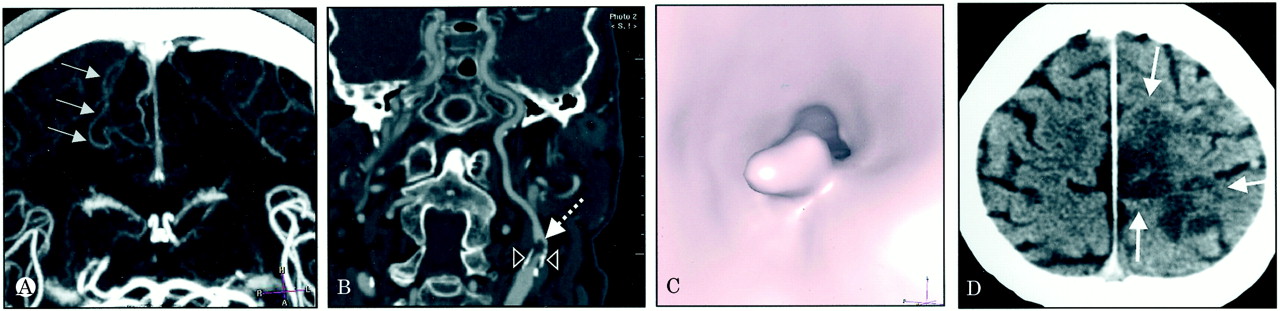

61岁的高血压的人提出了1小时后突然出现右侧偏瘫和hemineglect。头部CT是不起眼的,但是多层螺旋CT血管造影(MS-CTA)证明左大脑前动脉(ACA)同侧颈内动脉(ICA)分支闭塞和狭窄的管腔内的血栓(图中,通过C)。因此,系统性和重组组织纤溶酶原激活物开始溶栓。第二天,头部CT描绘一个小皮质ACA梗死(图D)。

图。脑多层螺旋CT血管造影(MS-CTA):正常大脑前动脉(ACA)外围分支(箭头),右边相应侧分支(A)的低灌注。颈MS-CTA:左颈内动脉狭窄(B)与澄清(箭头)和管腔内的血栓(虚线箭头);内腔血栓(C)的视图显示顶端。(D)头部CT:皮质ACA梗死影响靠近中央的前线和顶叶(箭头)。